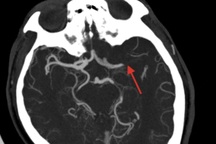

Bác sĩ Duy nhấn mạnh, thiếu máu não, đặc biệt là thiếu máu não cục bộ thoáng qua (TIA - Transient Ischemic Attack), là một dấu hiệu cảnh báo nguy hiểm.

"TIA xảy ra khi một mạch máu não bị tắc nghẽn tạm thời, thường do cục máu đông. Các triệu chứng có thể biến mất nhanh chóng, khiến người bệnh chủ quan, nhưng đây là dấu hiệu sớm của 12% các ca đột quỵ", bác sĩ Duy cảnh báo.

Thống kê cho thấy, khoảng 9-17% bệnh nhân trải qua TIA có nguy cơ đột quỵ trong vòng 90 ngày, và 12% ca đột quỵ có tiền sử TIA tử vong trong vòng một năm.